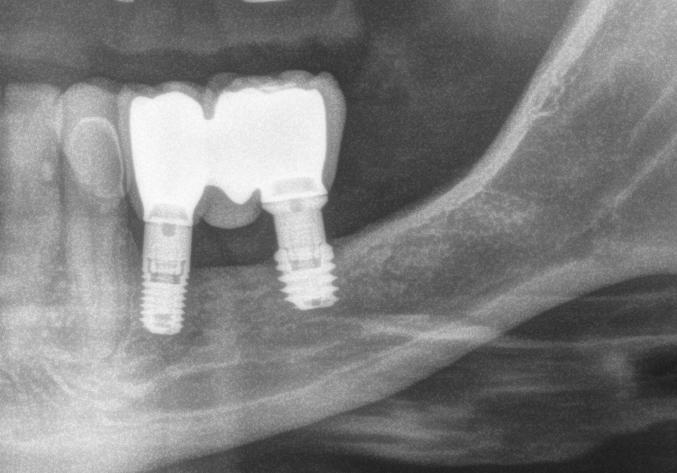

Radiografía a los 9 años